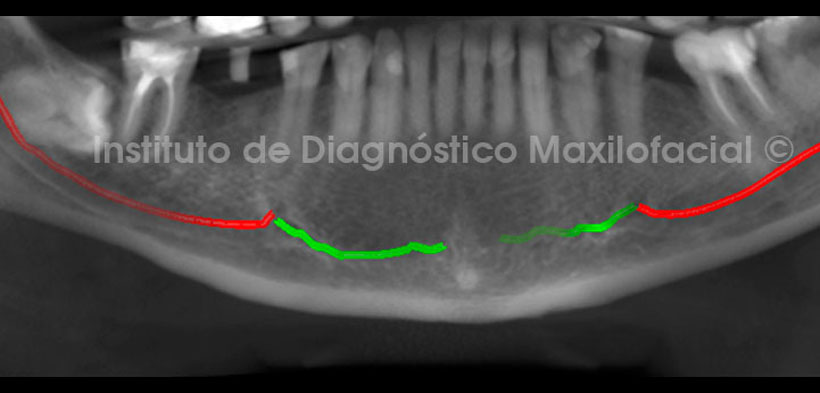

En la siguiente recontrucción panorámica se hizo un corte de mayor grosor para visualizar las piezas dentarias y la guía tomográfica. En consecuencia, se delimitaron ambos conductos mandibulares, siendo de color rojo el conducto dentario inferior y de color verde el conducto incisivo mandibular. Nótese que en ambos cortes se observa la pieza 4.8 impactada en posición horizontal y su porción radicular próxima al coducto dentario inferior.